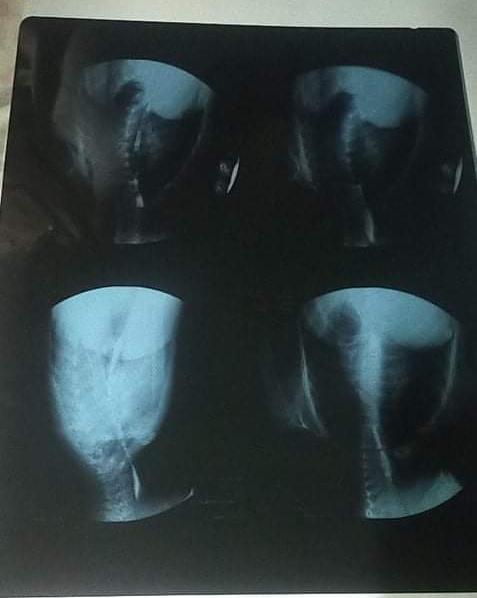

وتابع إبراهيم: كانت تشكو من ضيق التنفس، حتى تم عمل منظار لها اكتشف الأطباء به وجود غشاء بين البلعوم والقصة الهوائية، لذا قرروا إجراء عملية شق حنجري.

وواصل والد الطفلة: بعد كده عملت عملية المنظار الثاني جسمها مقبلوش ومعرفوش يعملوه، وقال الدكاترة هنخرم أنبوبة معدية في بطنها، وحاولوا يوسعوا من تحت الأنبوبة لكن معرفوش.